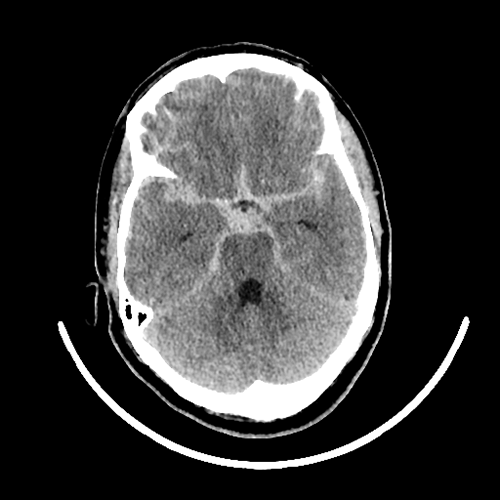

くも膜下出血の単純CT- 脳卒中 (脳出血・くも膜下出血・脳梗塞)

「突然手がうまく動かせなくなった」「頭が痛い」などでみつかった脳卒中や、人間ドックで偶然見つかった脳動脈瘤などが対象となります。診察後、CT・MRI・血管造影などの検査を行い、どのように治療していくか決めていきます。

ちなみに、脳動脈瘤の場合、患者さん本人の状態と検査結果をみて、経過観察 (定期的に様子をみていく)をするか手術 (開頭クリッピング術 または 脳血管内手術)をするか決めていきます。